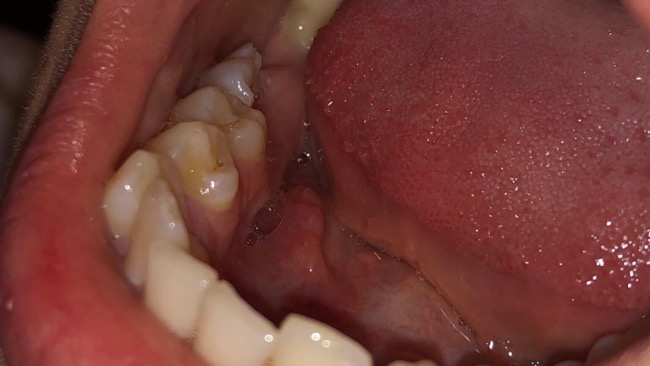

(Na zdjęciach widać brak już jednego zęba (7). Kanały nie są dostatecznie wypełnione do końca.)

Co robić ? Zęby coraz słabsze, zaczynają kruszyć się nawet przy delikatnym zgryzie.

Kolejne nowe wiadomości - pozostałe sąsiadujące zęby coraz słabsze. To koniec. Ostatnia a zarazem najkosztowniejsza deska ratunku - WSZCZEPIENIE IMPLANTÓW. Skąd uzbierać tak ogromną sumę? Dla Magdy było to nierealne. A co jeśli się nie przyjmą? 24 lata - nikt nie spodziewa się w swoim życiu takich sytuacji. Stres spowodowany całym zdarzeniem tylko pogarszał już i tak beznadziejną sytuację. Wszystkie marzenia w jednej chwili przestały mieć jakiekolwiek znaczenie. NOWE ZĘBY - to w tej chwili jest najważniejsze !